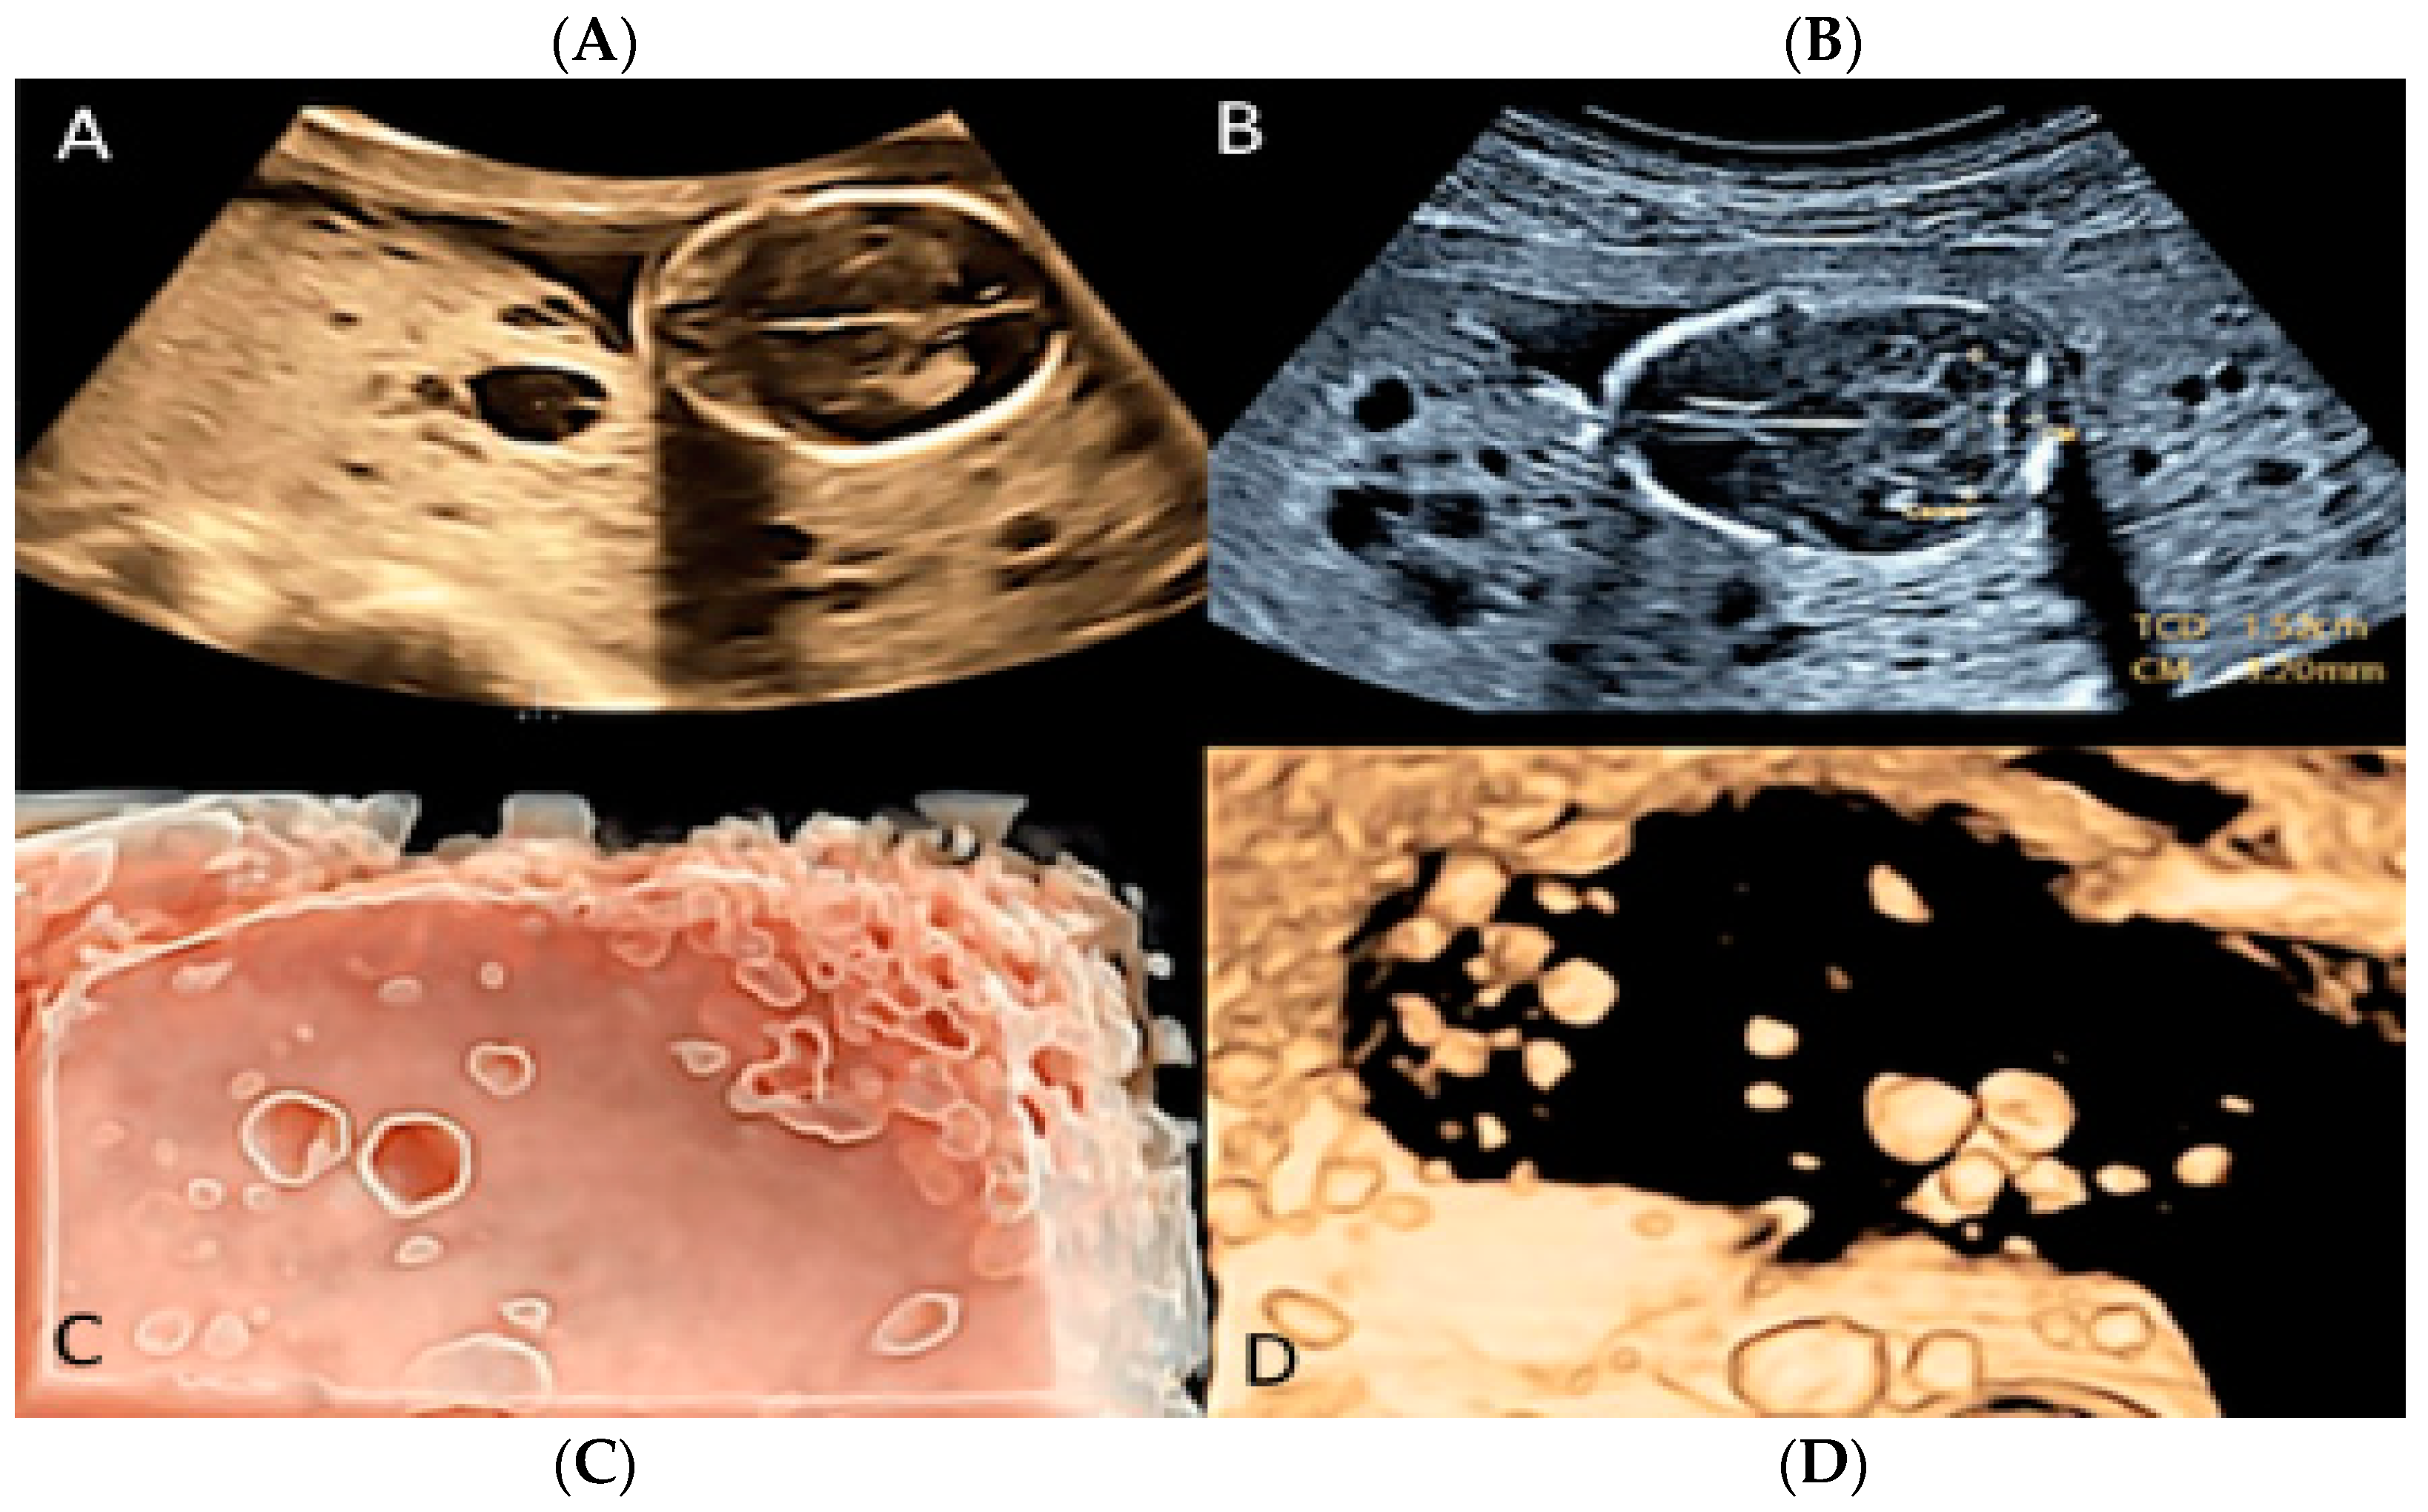

3.1.5. Placental Mesenchymal Dysplasia

Placental mesenchymal dysplasia is a rare vascular anomaly of the placenta characterized by cystic lesions, mesenchymal villous hyperplasia, and the thrombosis of the chorionic plate and stem villous vessels [27,37,38]. Sonographic diagnosis includes placentomegaly and a “grape-like” placental appearance, with multiple cystic areas, making a differential diagnosis with gestational trophoblastic disease (GST) a challenging issue [27,37,38,39]. Placental mesenchymal dysplasia may be seen to be associated with fetal growth restriction (FGR), intrauterine fetal demise (IUFD) and preterm delivery [27]. (Figure 11).

Figure 11.

Placental with mesenchymal dysplasia at 15 weeks of gestation. Two-dimensional (A,B) and three-dimensional ultrasound (C,D) with HD-Live Silhouette™ and inversion mode displaying a characteristic large placenta with “grape-like”, multicystic changes.